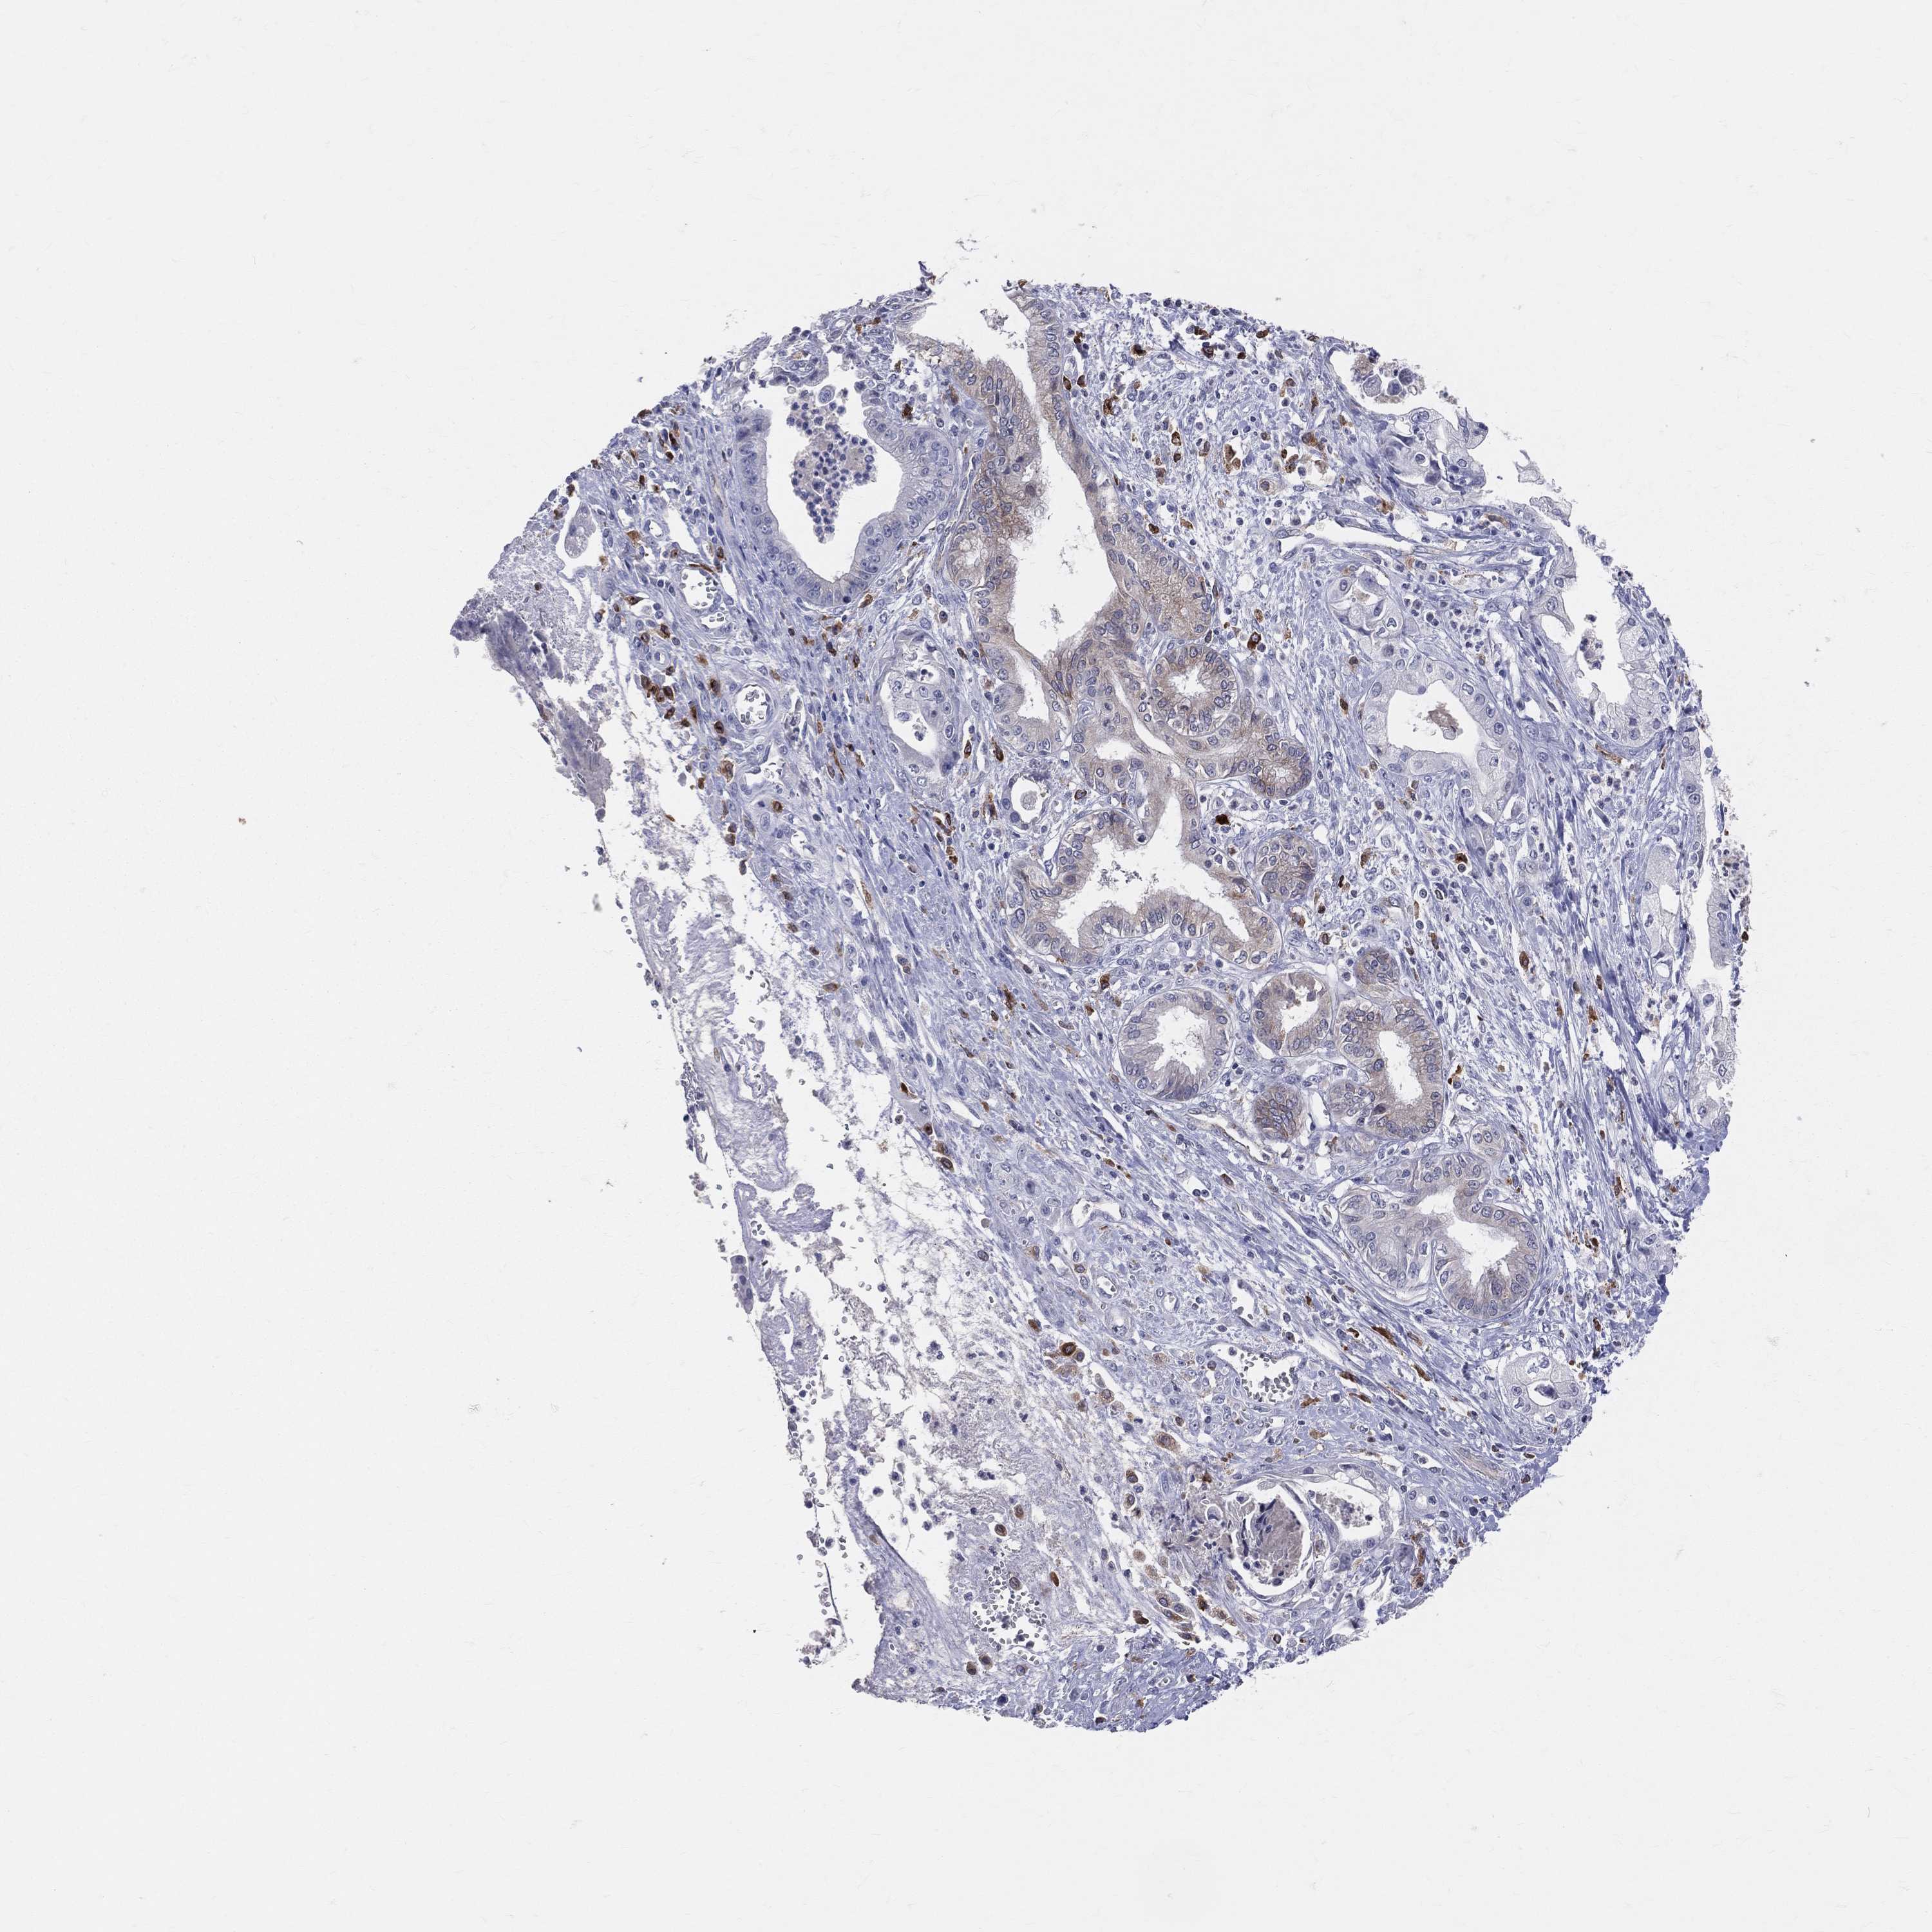

PANCREATIC CANCER - Protein expressioni

A mouse-over function shows sample information and annotation data. Click on an image to view it in a full screen mode. Samples can be filtered based on level of antibody staining by selecting one or several of the following categories: high, medium, low and not detected. The assay and annotation is described here.

Note that samples used for immunohistochemistry by the Human Protein Atlas do not correspond to samples in the TCGA dataset.

Antibody stainingi

Antibody staining in the annotated cell types in the current human tissue is reported as not detected, low, medium, or high, based on conventional immunohistochemistry profiling in selected tissues. This score is based on the combination of the staining intensity and fraction of stained cells.

Each image is clickable and will lead to virtual microscopy that enables deeper exploration of all samples and also displays staining intensity scores, fraction scores and subcellular localization as well as patient and tissue information for each sample.

Antibody HPA010592

Antibody CAB002506

Antibody CAB079994

Adenocarcinoma, NOS

Adenocarcinoma, metastatic, NOS